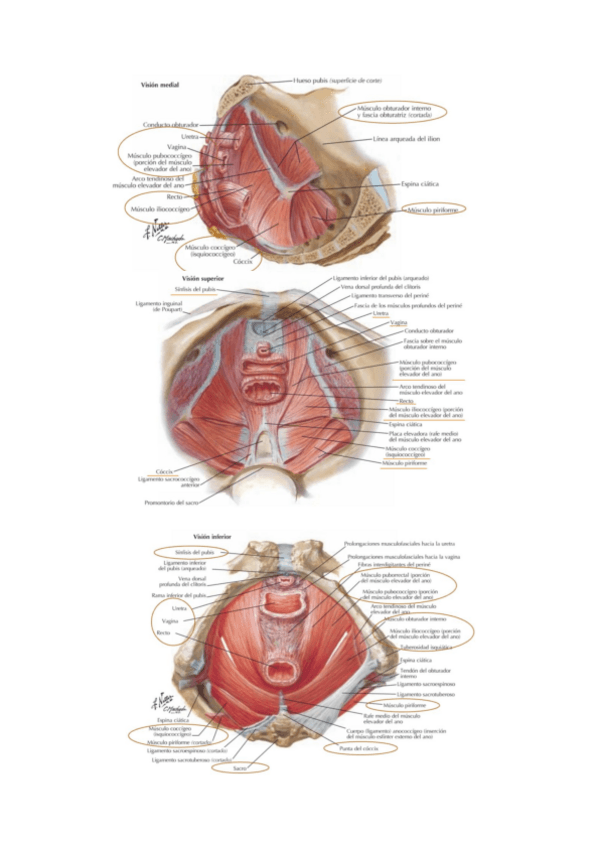

He publicado nuevos apuntes de Anatomía por la imagen: Sistema-MUSCULAR.pdf

11 páginas

He publicado nuevos apuntes de Anatomía por la imagen: TEMA-8-pelvis-sistema-genital.pdf

9 páginas